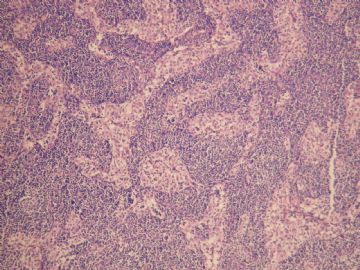

简要病史:  女   55岁临床病史:发现左颈淋巴结肿大一周,双颈及腋下可扪及多个肿大淋巴结.

手术所见:胸锁乳突肌深面多个肿大淋巴结,成簇、质中等、与周围无粘连。

巨检:淋巴结一个,1.3×0.7×0.6cm,切面灰白。

• 左颈淋巴结肿大图1

图1

老年女性,全身多发 淋巴结肿大,图1见深染区和浅染区,图2 和3见生发中心血管植入,呈蚊香样结构,图4,5见组织细胞增生,未见吞噬现象,淋巴结髓索和窦境界存在,见滤泡结构,首先考虑淋巴结反应性增生病变(窦性增生),但要排除castlamen病可能

老年女性,全身多发 淋巴结肿大,图1见深染区和浅染区,图2 和3见生发中心血管植入,呈蚊香样结构,图4,5见组织细胞增生,未见吞噬现象,淋巴结髓索和窦境界存在,见滤泡结构,首先考虑淋巴结反应性增生病变(窦性增生),但要排除castlamen病可能,浆细胞不明显